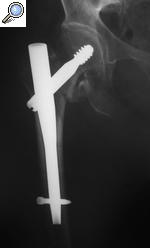

En el caso de las fracturas extracapsulares lo que solemos utilizar en el quirófano son “clavos de osteosíntesis”. Una imagen vale más que mil palabras. De nuevo no os voy a hablar del tipo de clavos ni de cuestiones técnicas. Ya en otro post os he hablado de ellos resaltando la importancia que tienen para salvar vidas de forma constante. Es curioso porque es de los post menos seguidos, muchísimo menos que cuando hablamos de meniscos o ligamentos, ¿no os parece significativo?